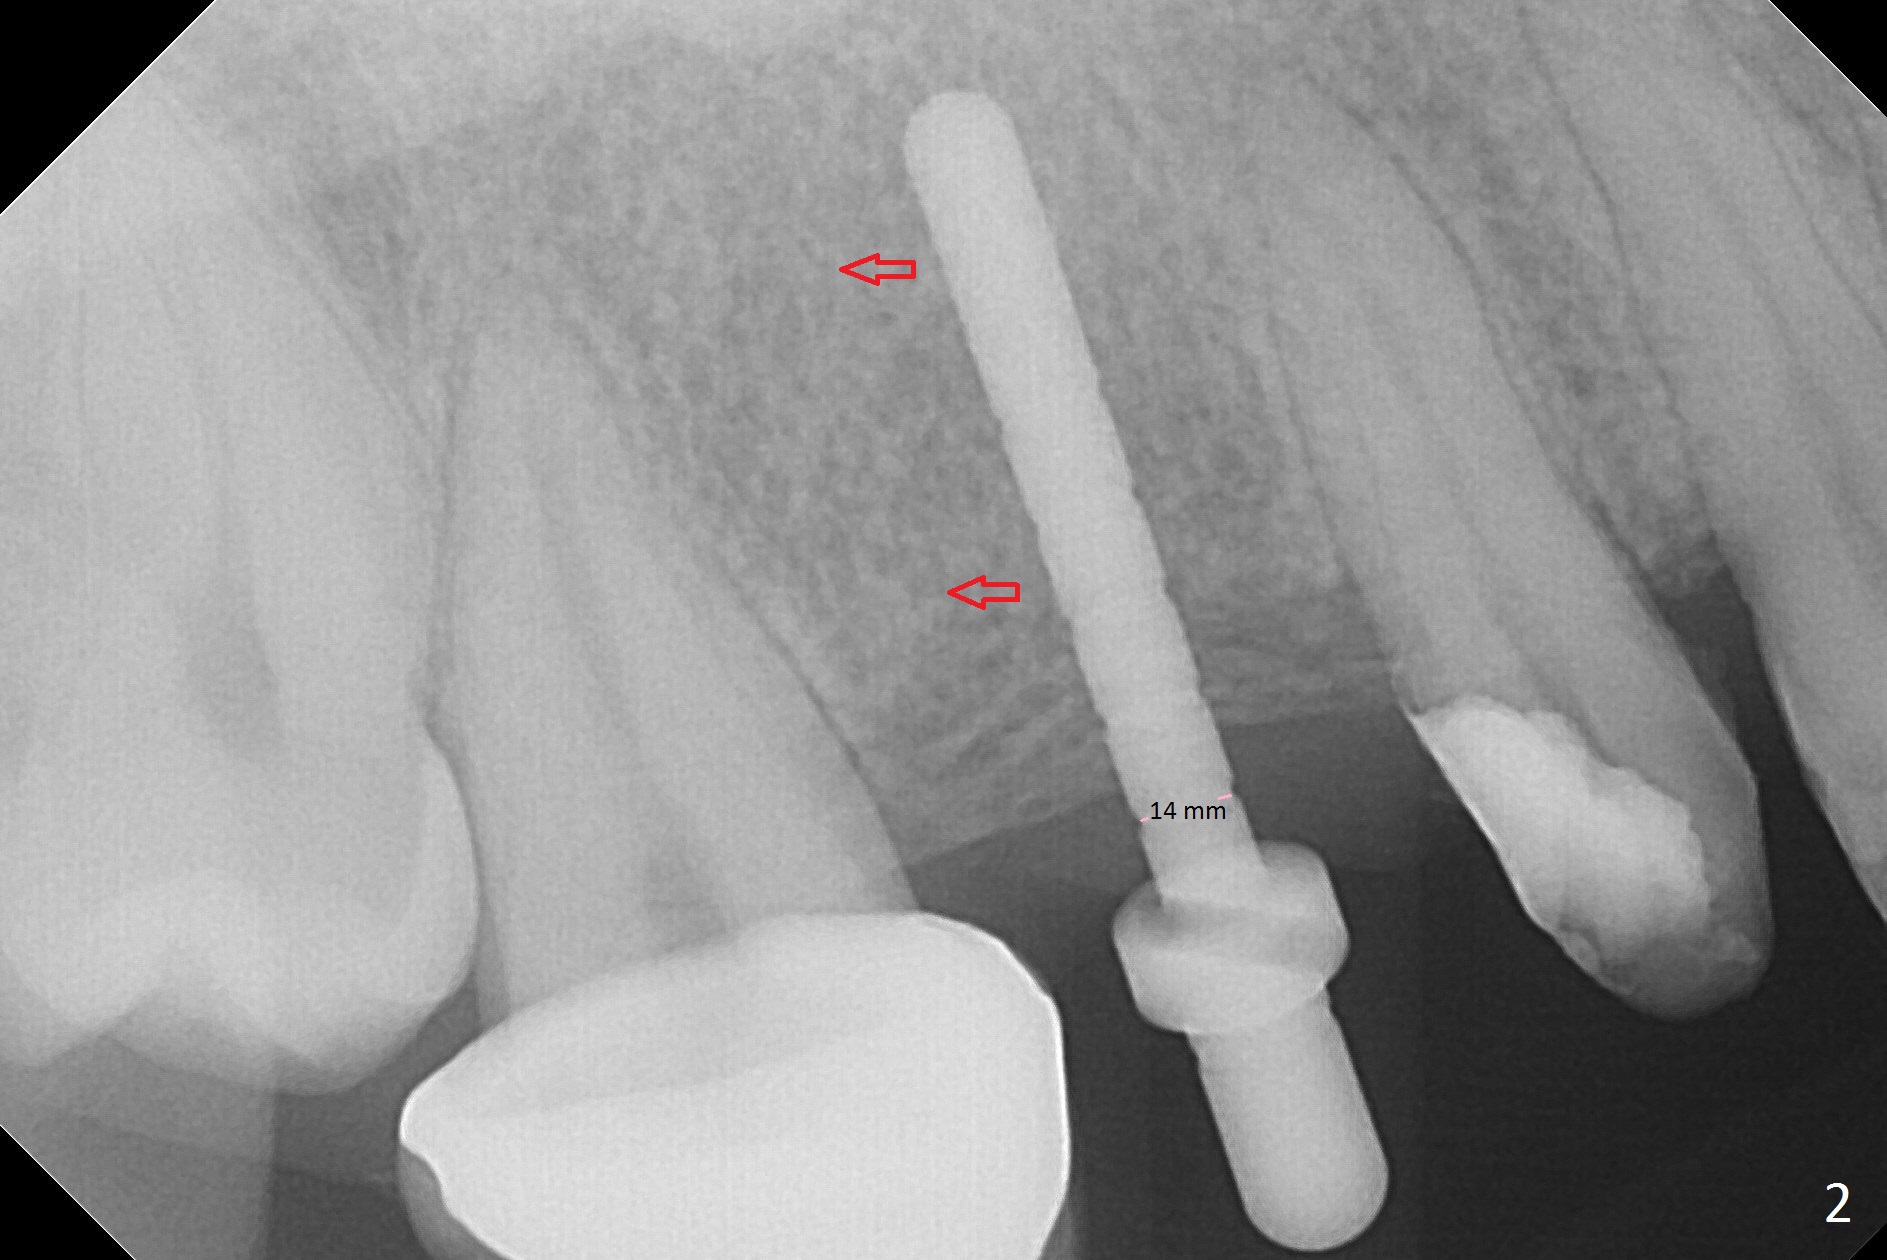

When the bridge is partially removed, the tooth #4 is found to have extensive caries. IRM is placed following carious removal (Fig.1). Magic Split testing shows that the bone density is high (flapless). Osteotomy is initiated by 1.6 mm drill, but the handle of the drill needs to shift mesial (Fig.1 red arrow). When the latter is done, the whole drill (2 mm) needs to move distal (Fig.2 double red arrows). When a 4.5x14 mm drill finishes the osteotomy, it is in the middle of the edentulous space (Fig.3). After use of 5 mm tap, a 5.3x14 mm implant cannot reach the depth (Fig.4,5). Following increase in osteotomy depth from 16 to 18 mm (gingival margin) until 5 mm drill in diameter, the implant placement level is more ideal (Fig.6,7, slightly subcrestal) with insertion torque maintaining at >55 Ncm. The sinus floor (Fig.4 arrowheads) may be penetrated when the osteotomy depth increases (Fig.7 *), but the sinus membrane remains intact.